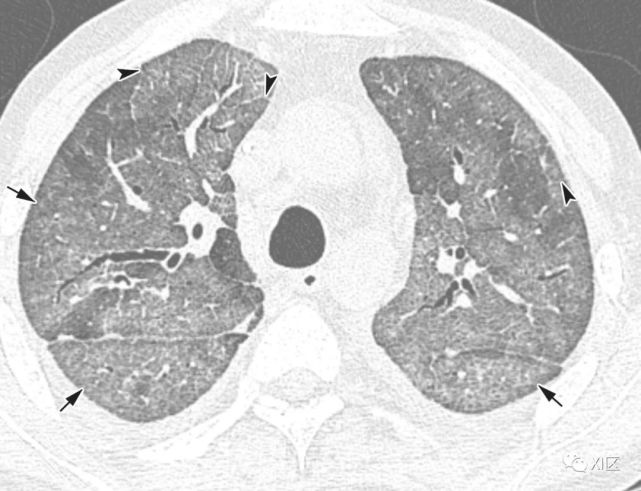

在需要进入重症监护室的重症肺炎患者中,人鼻病毒是最常见的病毒病原体。在重度鼻病毒性肺炎患者中,注意到双侧斑片状实变伴多灶性GGO和小叶间隔增厚

图26 51岁的急性髓细胞性白血病患者,因鼻病毒引起的肺炎,在骨髓移植后3个月出现呼吸困难。

(a)最初的胸部X线照片显示两个肺部均出现不规则的,不明确的斑片状不透明性增加(箭头)。 (b,c)同一天在较低气管水平(b)和两个较低肺叶基底节段(c)上获得的轴向CT图像显示不透明区域不透明,小叶间隔增厚(箭头)和不明确的斑块状GGO( 箭头)。

51岁急性髓系白血病患者,骨髓移植后3个月出现呼吸困难,因鼻病毒引起肺炎。(上) 最初的胸片显示两肺不规则的模糊斑片状不透明度增加(箭头)。在同一天的较低气管水平(中)和两肺下叶基底段(下)轴位向CT图像显示两肺不规则的不透明度增加区域,肺小叶间隔增厚(箭头)和不明确的斑状GGO(箭头)。